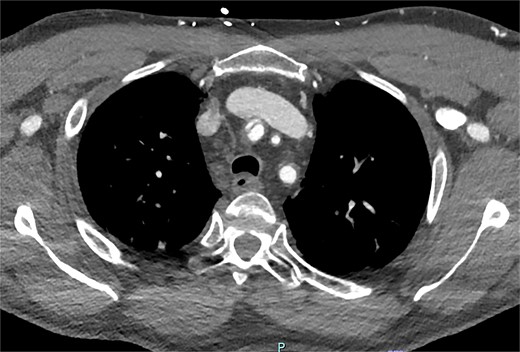

On arrive to the emergency department, the patient was found to be hypertensive with a blood pressure of 220/120 mmHg. Physical examination of the patient revealed no significant clinical findings. Serial troponins with corresponding ECG’s were undertaken which demonstrated no new evidence of myocardial ischaemia. Based upon the patient’s symptomatology, he underwent a CT aortogram which demonstrated a dissection arising from the proximal brachiocephalic artery. No dissection was noted in the ascending aorta, and there was no evidence of the brachiocephalic artery dissection extending into the subclavian or carotid arteries (Figs 1–3).

Axial slice from CT aortogram demonstrating the proximal aspect of the dissection flap.